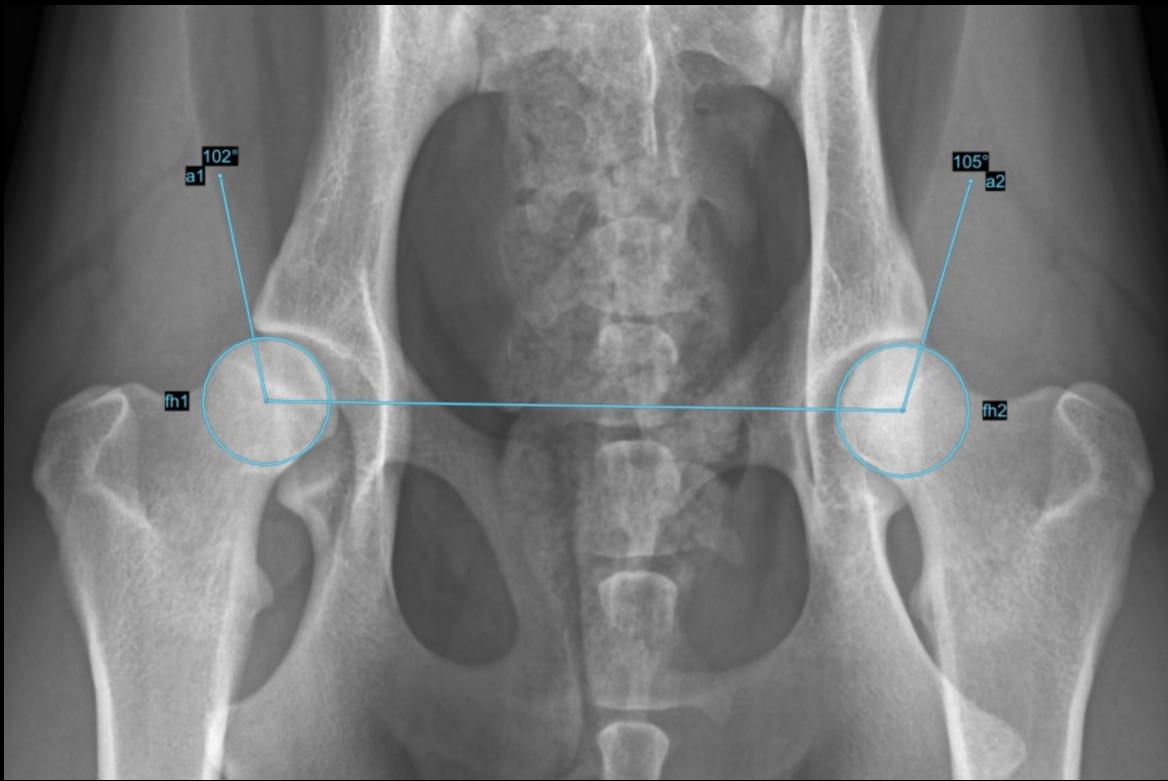

Hip Dysplasia Dog Norberg Angle . Hip dysplasia is the most common orthopedic condition of the dog, causing joint inflammation and secondary osteoarthritis, which lead to variable degrees of clinical discomfort. The angle between these lines is the. The norberg angle and the percentile rank accurately discriminated between dogs with or without canine hip dysplasia, with positive and negative likelihood ratios of 6·31 and. Then take the center of the femoral head and draw a line to the outer point of the pelvis. 66 genetically, it is a disease of complex inheritance, meaning that multiple genes, combined with environmental influences, ultimately cause expression of the condition. Extended hip and abducted hind limb radiographs performed at 1 year of age (18 months for large breed dogs) are scored according to the official. The norberg angle and the percentile rank accurately discriminated between dogs with or without canine hip dysplasia, with positive and.

Automatic Measurement of Norberg Hip Angles YouTube Hip Dysplasia Dog Norberg Angle The angle between these lines is the. 66 genetically, it is a disease of complex inheritance, meaning that multiple genes, combined with environmental influences, ultimately cause expression of the condition. The norberg angle and the percentile rank accurately discriminated between dogs with or without canine hip dysplasia, with positive and negative likelihood ratios of 6·31 and. Hip dysplasia is the. Hip Dysplasia Dog Norberg Angle.

Automated Measurements for Norberg Hip Angle with AI Software Hip Dysplasia Dog Norberg Angle Hip dysplasia is the most common orthopedic condition of the dog, causing joint inflammation and secondary osteoarthritis, which lead to variable degrees of clinical discomfort. 66 genetically, it is a disease of complex inheritance, meaning that multiple genes, combined with environmental influences, ultimately cause expression of the condition. Extended hip and abducted hind limb radiographs performed at 1 year of. Hip Dysplasia Dog Norberg Angle.

NorbergWinkel / Hip Displasia Measurement SmartPACS Hip Dysplasia Dog Norberg Angle The norberg angle and the percentile rank accurately discriminated between dogs with or without canine hip dysplasia, with positive and negative likelihood ratios of 6·31 and. Hip dysplasia is the most common orthopedic condition of the dog, causing joint inflammation and secondary osteoarthritis, which lead to variable degrees of clinical discomfort. The norberg angle and the percentile rank accurately discriminated. Hip Dysplasia Dog Norberg Angle.